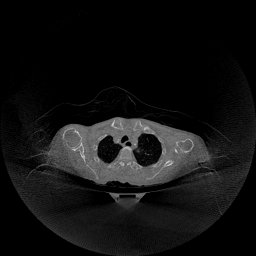

III-D Real Clinical Data Experiment

The experimental results on clinical head data are shown in Fig. 4. The reference images were reconstructed using the fast iterative shrinkage-thresholding algorithm (FISTA) with total variation regularization from non-truncated projection data. In the WCE reconstructions (Fig. 4(b)), severe truncation prevents accurate recovery of anatomical structures outside the FOV. Despite being trained solely on simulated data with a domain gap, all deep learning models can restore a substantial portion of the missing anatomy. Among them, the diffusion-based methods recover soft-tissue boundaries more faithfully than the conventional deep learning approach FBPConvNet, highlighting their stronger image generation capability. However, cDDPM reconstructions exhibit more noticeable noise than those from other methods, consistent with the simulated data results. The patchDiffusion model introduces artifacts within the FOV, likely due to its patch-wise processing strategy. While I2SB shares the same limitations as other diffusion models in perfectly restoring soft-tissue detail, it produces fewer residual noise patterns and fewer artifacts within the FOV boundaries. Overall, Fig. 4 demonstrates the strong efficacy of I2SB in reconstructing real CBCT data.